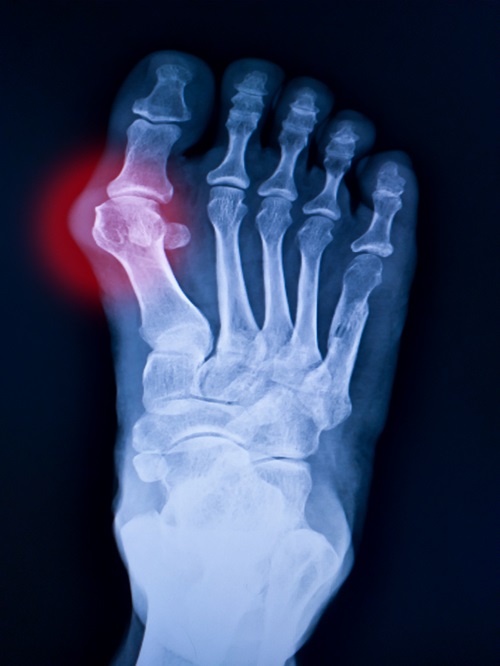

Fractures: Broken bones in the foot or ankle caused by falls, accidents, or impact.